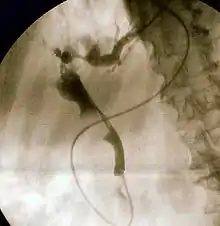

![]() Duodenoscopía que muestra la salida de pus de la ampolla de Vater, un hallazgo clínico de Colangitis. | ||

- Colangiopancreatografía retrógrada endoscópica. Confirma la obstrucción y el nivel, permite la recolección de especímenes para su cultivo y citología, es la indicada para el diagnóstico si la ultrasonografía y la tomografía axial computarizada no han sido concluyentes. Puede ser indicada como parte de la terapéutica.[1][4][2]

Colangiopancreatografía retrógrada endoscópica

Es el procedimiento de elección. El paciente debe ser estabilizado lo más que se pueda antes del procedimiento, y la hidratación e inicio inmediato de antibióticos son requeridos. Deben explorarse los antecedentes del paciente para identificar alteraciones anatómicas (como cirugías o malformaciones) que dificulten o imposibiliten el acceso. Los pacientes graves pueden requerir una CPRE de emergencia con apoyo de un fluoroscopio móvil en la unidad de cuidados intensivos (aunque se han realizado descompresiones sin el mismo). Cuando se realiza el procedimiento, el material purulento debe ser retirado del área para evitar complicaciones. El uso de medios de contraste debe ser limitado. Para descomprimir, la canula debe drenar entre 20 y 40 mL que servirán para un cultivo biliar. Después del drenado, debe localizarse la obstrucción a menos que se sospeche de colestasis intrahepática. Por este procedimiento puede conseguirse una remoción de cálculos en pacientes estables con el diagnóstico confirmado de cálculos en los conductos biliares[4]